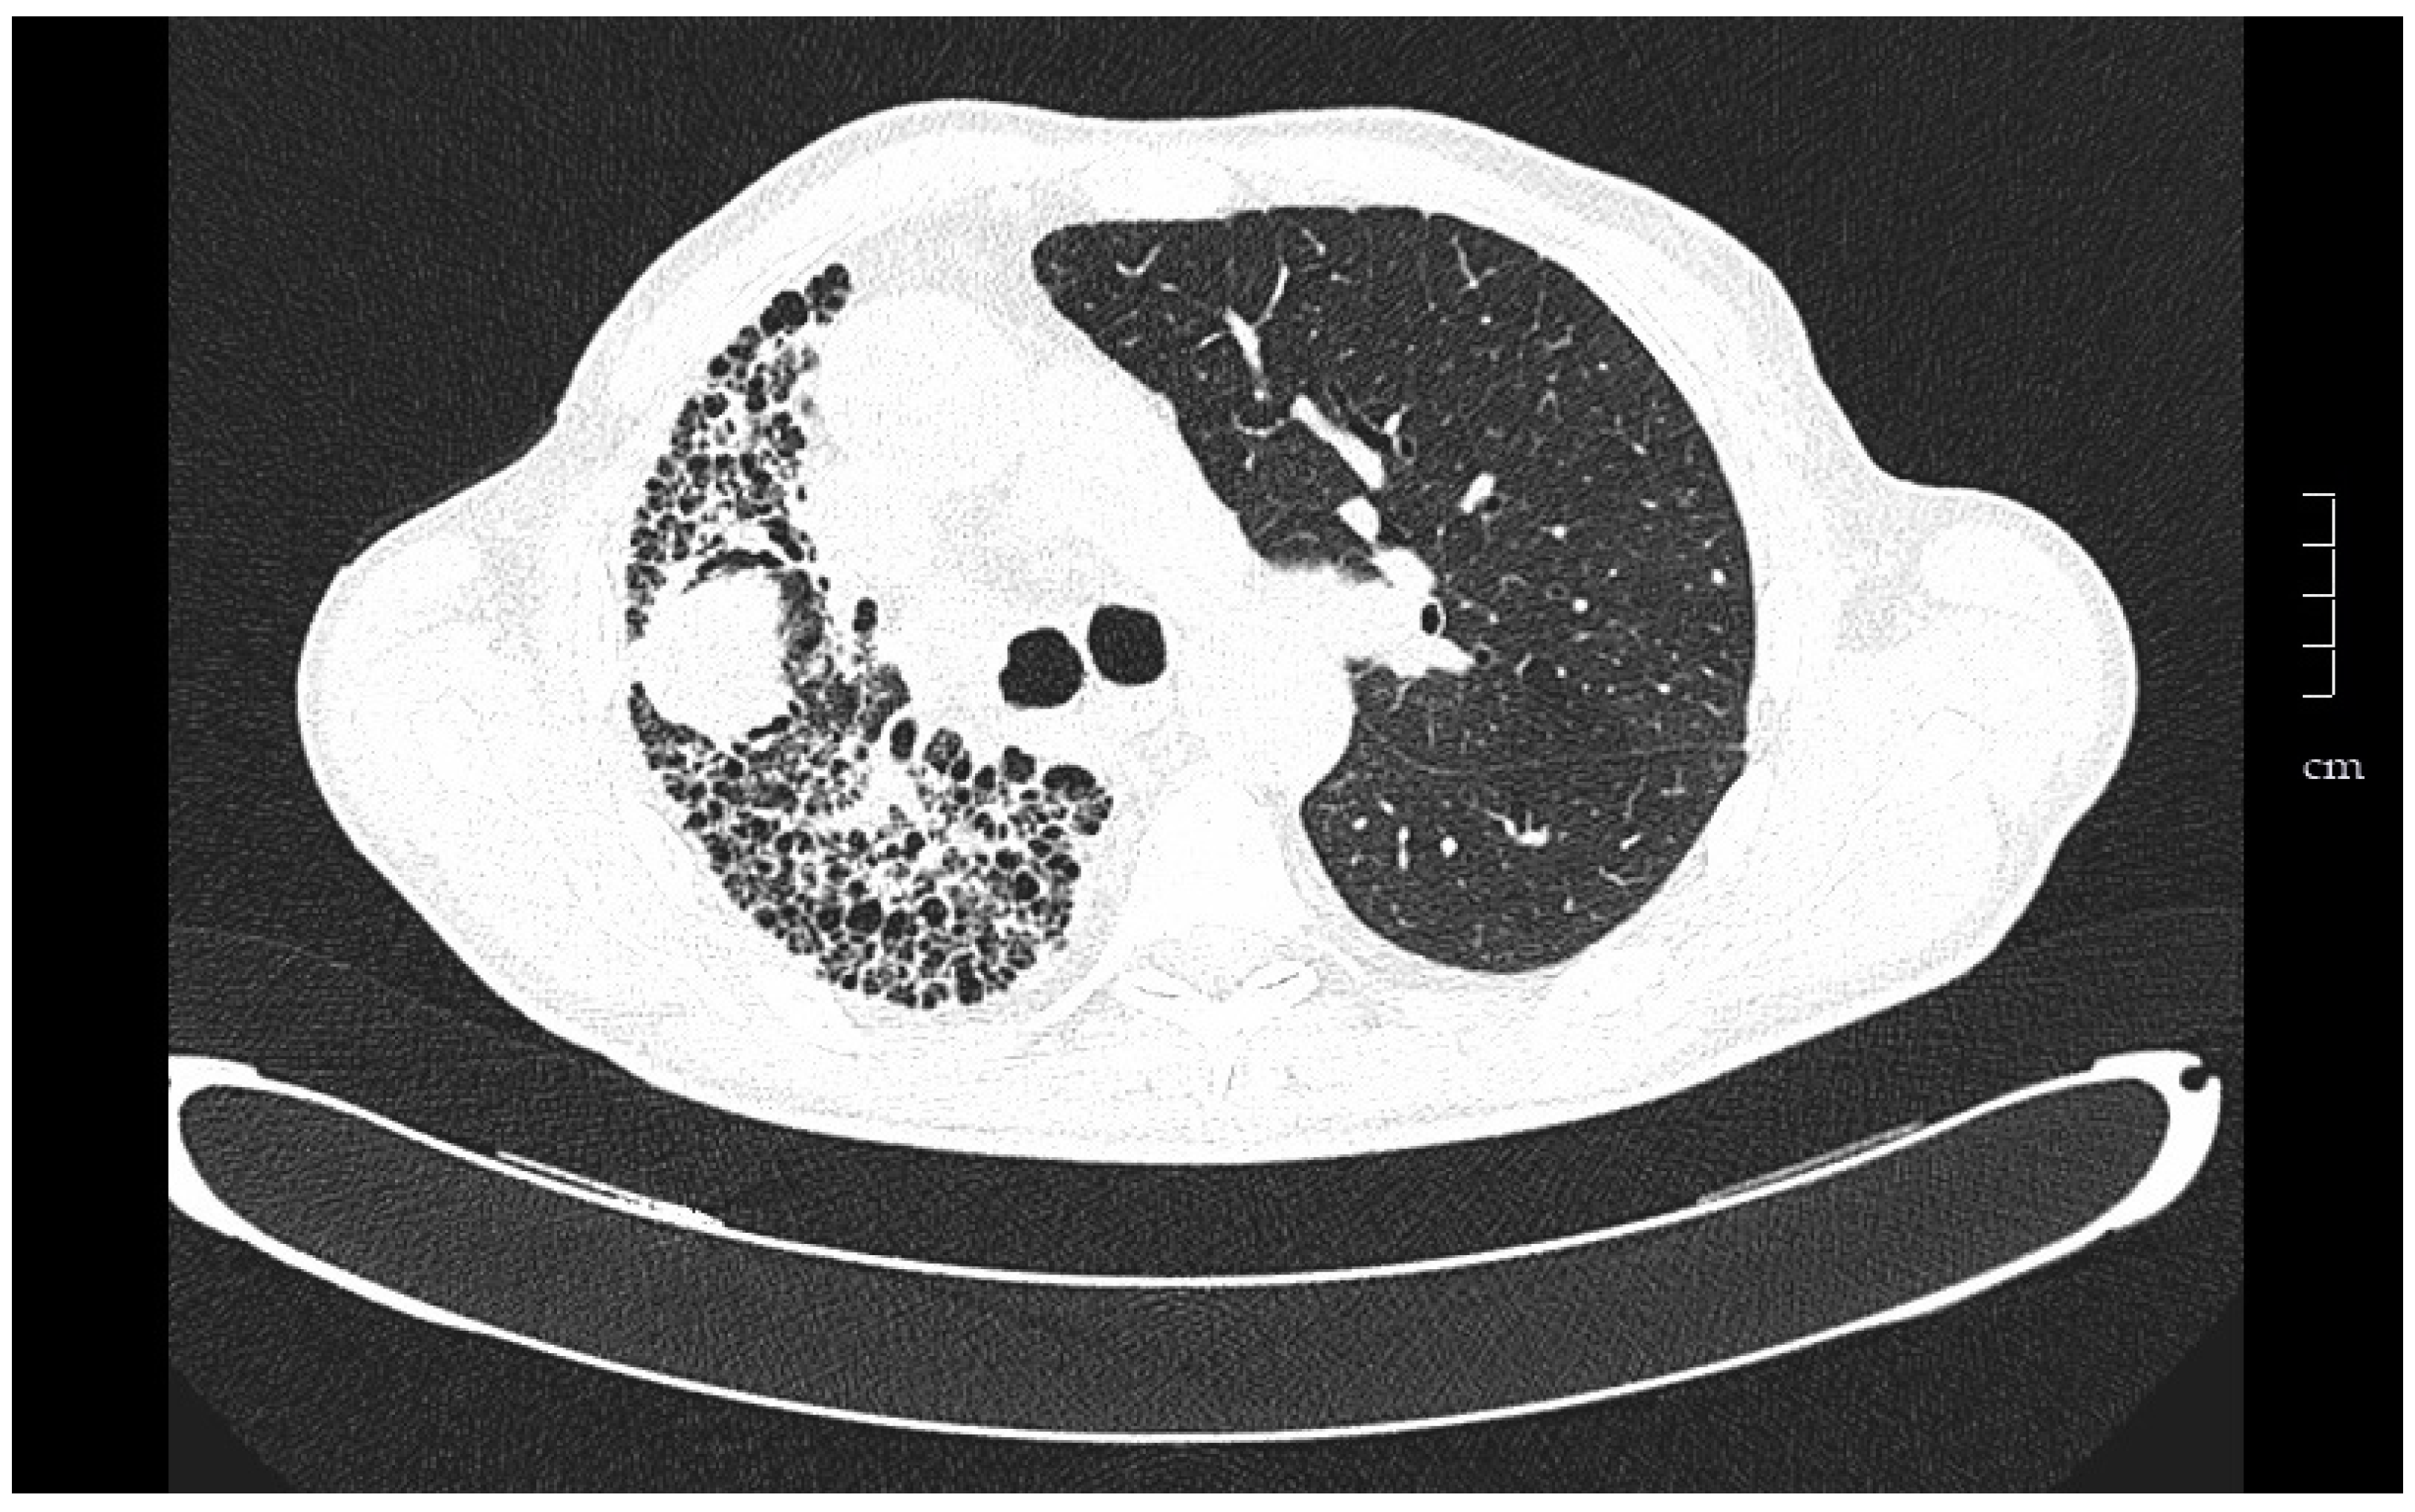

| Histopathologic diagnosis of UIP or fibrotic NSIP |